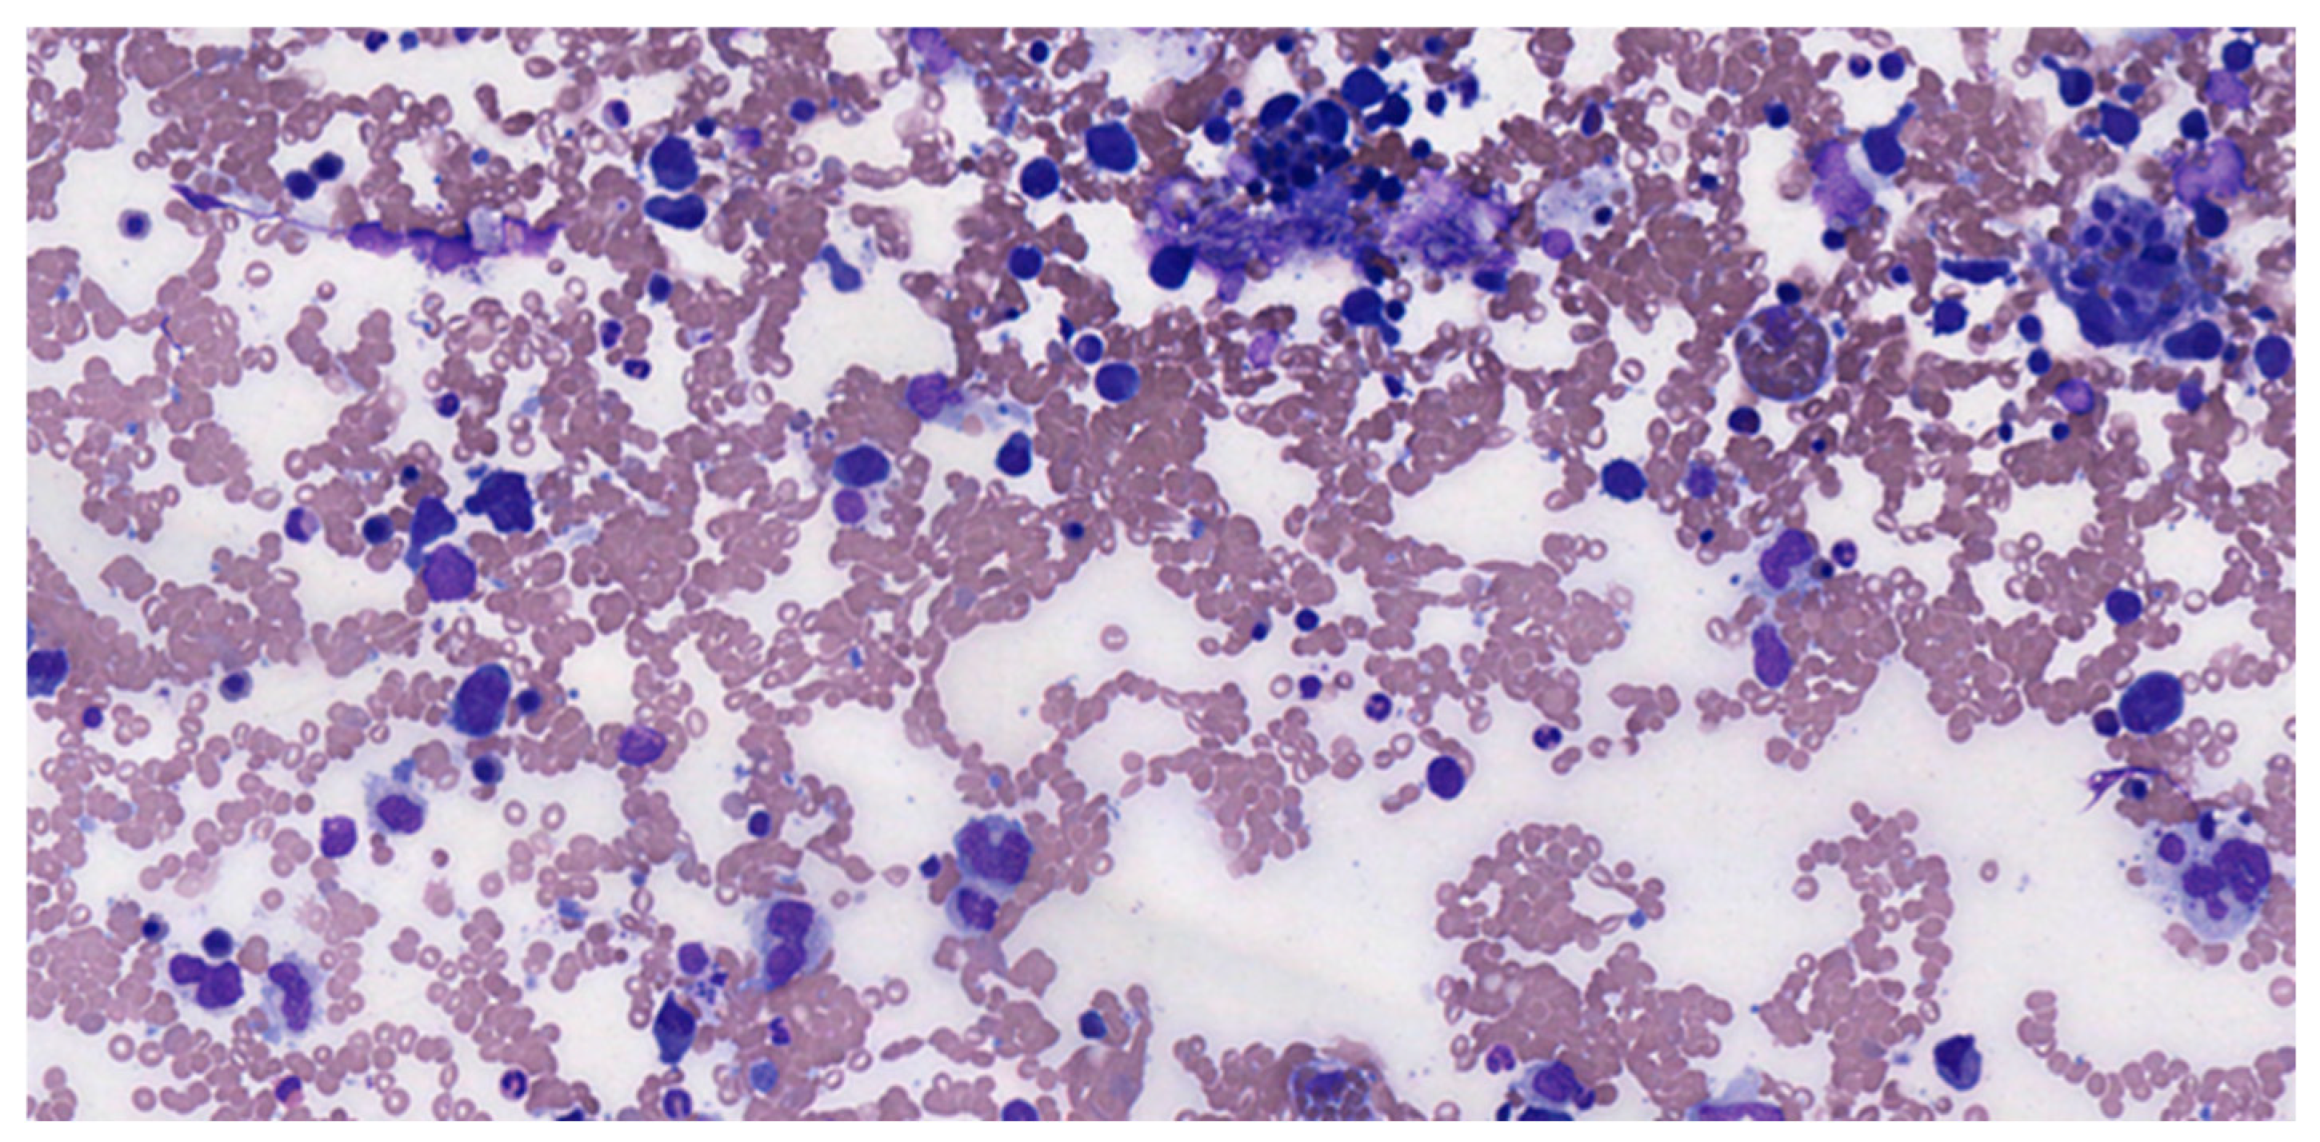

4. Histological Characteristics and Developmental Patterns

5. Morphological Evaluation